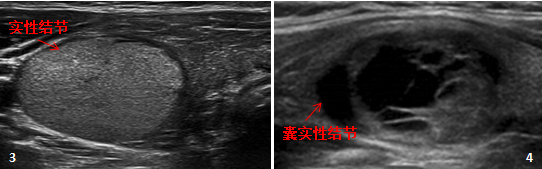

“实性或近实性结节”完全或几乎由实性成分组成,仅含有少量囊性成分(图 3)。

“混合囊性实性”结节包括实性和囊性成分,以实性为主,以囊性为主,或两者比例相似(图4)。

评估囊实性结节最重要的是实性部分,其超声特征对于结节评估比结节大小和囊实性比例更重要。 如果实性部分偏心、边缘有角、低回声、分叶状、边缘不规则或点状强回声或血流信号,则恶性风险增加。